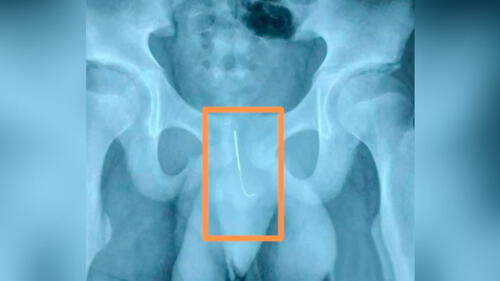

Le extrajeron la aguja en el hospital X'ian Children's. Foto: AsiaWire.

El médico Wang Shengxing examina la imagen de rayos x de la pelvis del menor. Foto: AsiaWire.

El jefe adjunto de urología en el hospital, Wang Shengxing, examinó al muchacho después de que lo trasladaron desde un hospital local más pequeño.

“Le dolió cuando caminaba y cuando orinaba. Su padres estaban bastante angustiados”, dijo el médico.

“Estaba en riesgo de infección o sangrado; si se hubiera movido, podría haberle roto la vejiga o las arterias”, explicó Wang.